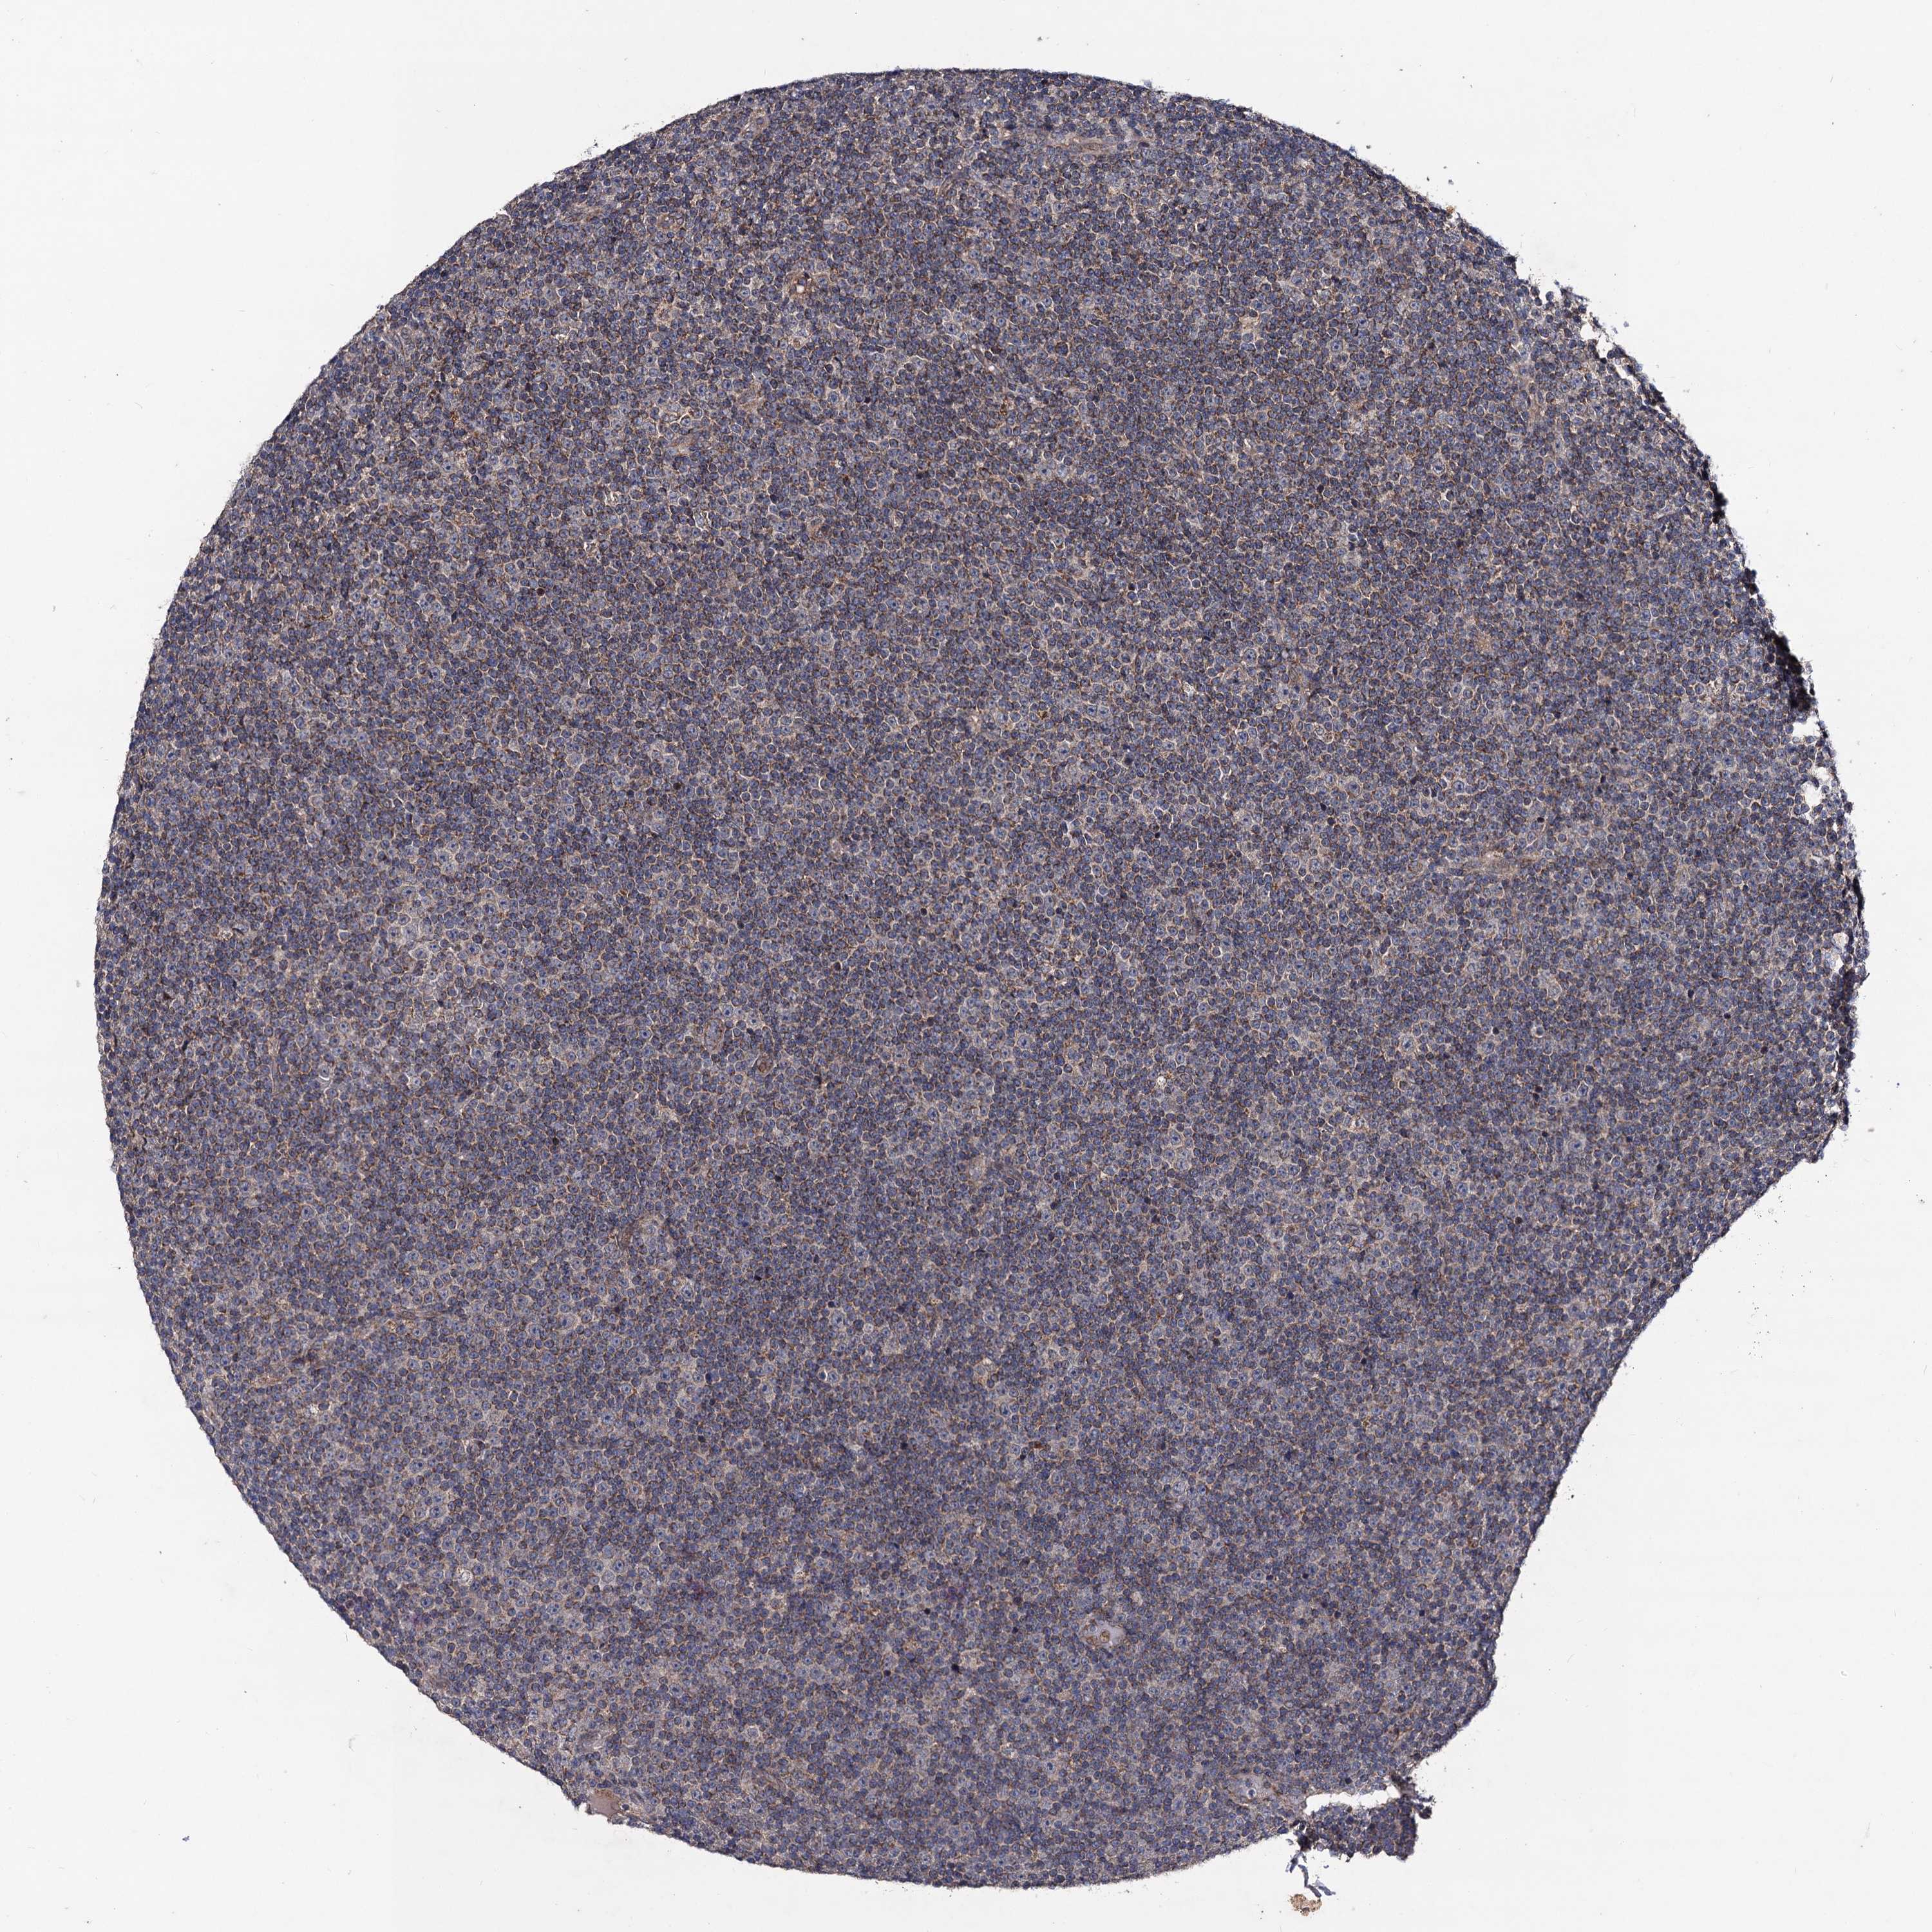

CANCER LYMPHOMA Show tissue menu

LYMPHOMA - Protein expressioni

A mouse-over function shows sample information and annotation data. Click on an image to view it in a full screen mode. Samples can be filtered based on level of antibody staining by selecting one or several of the following categories: high, medium, low and not detected. The assay and annotation is described here.

Antibody stainingi

Antibody staining in the annotated cell types in the current human tissue is reported as not detected, low, medium, or high, based on conventional immunohistochemistry profiling in selected tissues. This score is based on the combination of the staining intensity and fraction of stained cells.

Each image is clickable and will lead to virtual microscopy that enables deeper exploration of all samples and also displays staining intensity scores, fraction scores and subcellular localization as well as patient and tissue information for each sample.

Antibody HPA040978

Staining

High

Medium

Low

Not detected

Intensity

Strong

Moderate

Weak

Negative

Quantity

>75%

75%-25%

<25%

None

Location

Nuclear

Cytoplasmic/membranous

Cytoplasmic/membranous,nuclear

Hodgkin's disease, NOS

Malignant lymphoma, non-Hodgkin's type, High grade

Malignant lymphoma, non-Hodgkin's type, Low grade